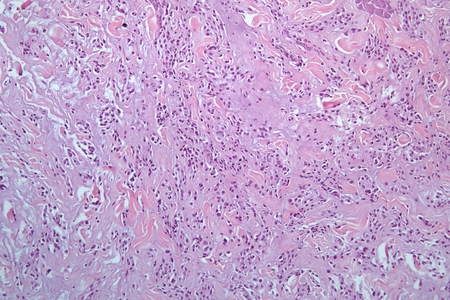

разработка методов микроскопической диагностики патологии соединительной ткани

и лимфатической системы, морфологической оценке эффектов лекарственных

Изучение структурных

особенностей изменений в соединительной ткани и лимфатической системе при

аутоиммунных и опухолевых заболеваниях.